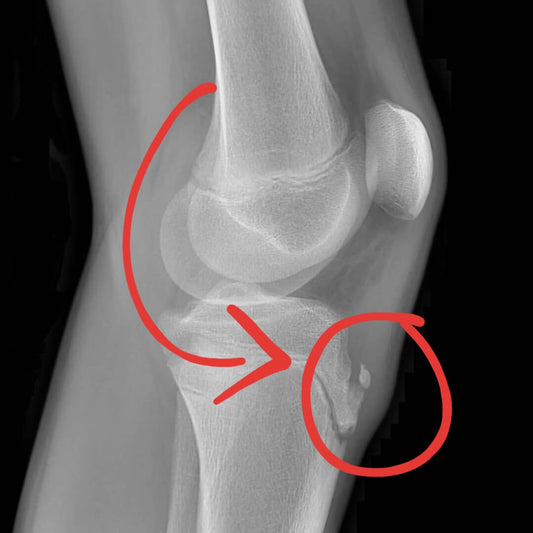

osgood schlatter disease xray

Osgood-Schlatter Disease: Why These "Growing Pa...

Osgood-Schlatter isn't just "growing pains." A physio explains the hidden spinal connection (T10-L3 stiffness) and how to treat it for lasting relief.